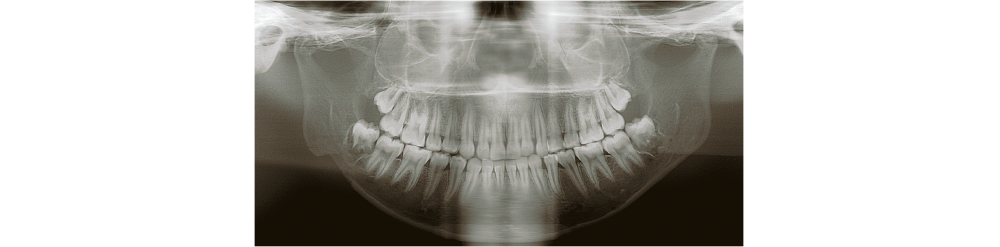

With dentists from various fields of expertise as advisors, we have carefully selected FOVs that are commonly used in clinical practice. In addition to the 3D analysis function for image detail sizes of 5x5cm, 10x10cm, 15x10cm and 15x16cm, the device features “True” and “Reconstructed” panoramic modes. With one of the largest FOVs on the market, the PreXion3D EXPLORER helps to develop the best therapy options, particularly in oral and maxillofacial surgery, airway analysis and orthodontics, as well as ear, nose and throat medicine. The use of a large 25.4x31.7cm FPD enables 15x16cm FOV scanning in one rotation.

The precise and high-resolution display of hard and soft tissue enables outstanding diagnostics and planning across all areas of modern dentistry and maxillofacial surgery. A large high-definition FPD allows all FOVs scanned in a single rotation without using stitching function.

With many 3D imaging systems on the market today, high-quality images are often accompanied by high radiation exposure. The PreXion3D EXPLORER offers balance of both aspects. The PreXion3D EXPLORER utilizes the industry’s smallest 0.3mm x-ray tube focal spot and voxel sizes from 0.07mm to 0.3mm for all FOV sizes. In addition, by adopting a high X-ray tube voltage of 110kV, pulsed X-ray irradiation, 16bit gray scale, and a newly developed large FPD, it simultaneously achieves high-definition image quality for a wide range of dental clinical practice and low radiation exposure for patient safety.